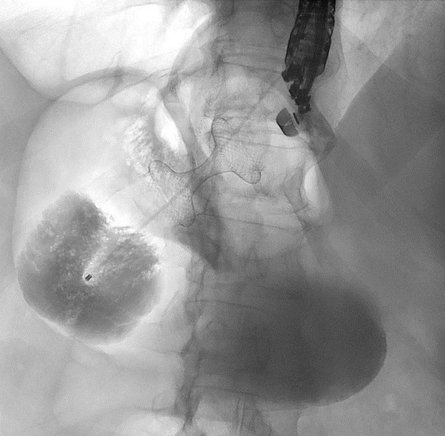

Anschließend wurde der ausgeschaltete Magen mit Flüssigkeit gefüllt und eine Verbindung zwischen dem kleinen Magenrest und dem ausgeschalteten Magen geschaffen (Abbildung 2).

Diese Verbindung wurde mithilfe eines speziellen Metallstents (LAMS, „Hot Axios“) angelegt. Da bei der Patientin keine akute Entzündung der Gallenwege bestand, konnte einige Tage abgewartet werden, bis sich der Stent vollständig entfaltet hatte. Über diesen neu geschaffenen Zugang war es anschließend möglich, die notwendige ERCP durchzuführen und die Gallensteine zu entfernen (Abbildung 3).